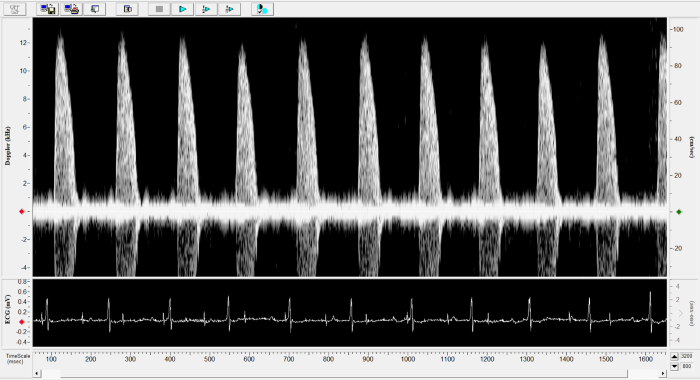

Imaging gallery - Doppler Flow Velocity System

Mouse - Abdominal Aorta. Image Credit: Scintica Instrumentation Inc.